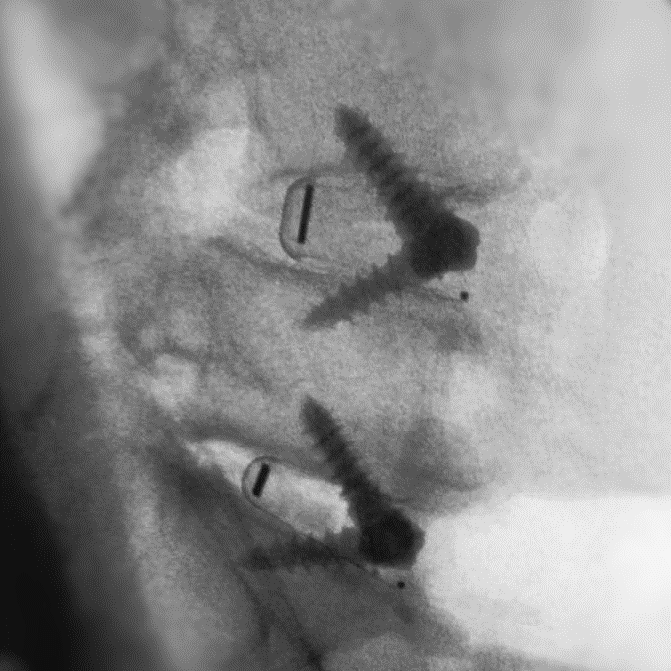

STALIF M™: Anterior fusion device for the lower (lumbar) spine (L2-S1), available in 3 material options (PEEK, PEEK with Ti-ACTIVE™, and FLX™)

The 1st implantation of a STALIF device took place in 1988. Since the very first device was implanted until now, Centinel Spine has continued to innovate and improve upon its original STALIF design, with state-of-the-art solutions now existing in multiple material options and device sizes to best suit each patient’s unique needs. The STALIF line of Integrated Interbody fusion implants are the longest implanted line of Integrated Interbody devices in the world.

STALIF devices come in a variety of material options to enhance opportunities for fusion based on patient specific needs. Some STALIF implants incorporate materials, such as titanium, that are known to be cell-friendly and attract bone cells. They also have very large cavities that allow for a large amount of bone to form between the vertebral bodies to make a solid fusion. Combining these features with the compressive design and the ability to pick an implant that fits each patient’s anatomy optimally enhances opportunities for successful fusion outcomes.